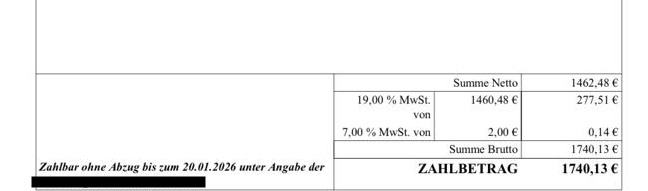

Allein die bisherige Rechnung der Tierklinik Leipzig beläuft sich auf rund 1.740 €.

Deshalb haben wir das Spendenziel auf 2.000 € festgelegt.